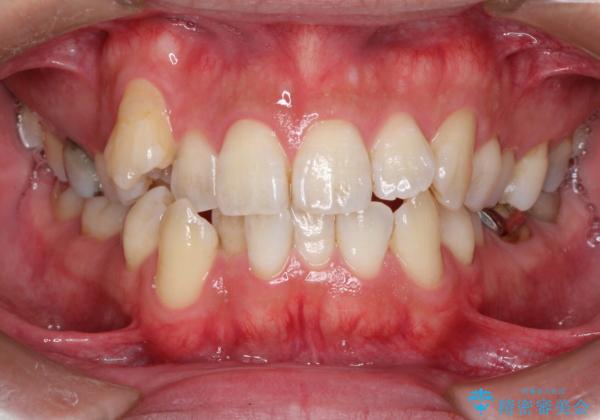

初診時の歯並びの状態としては、右上の犬歯がいわゆる八重歯の状態であり、強いガタガタが上下ともにある状態でした。

スペースの不足量が多く、抜歯を伴うワイヤー矯正にて治療を行いました。

若干の口元の突出感もあったため、抜歯によるスペースを利用し、がたつきの改善と前歯の後退をを行いました。